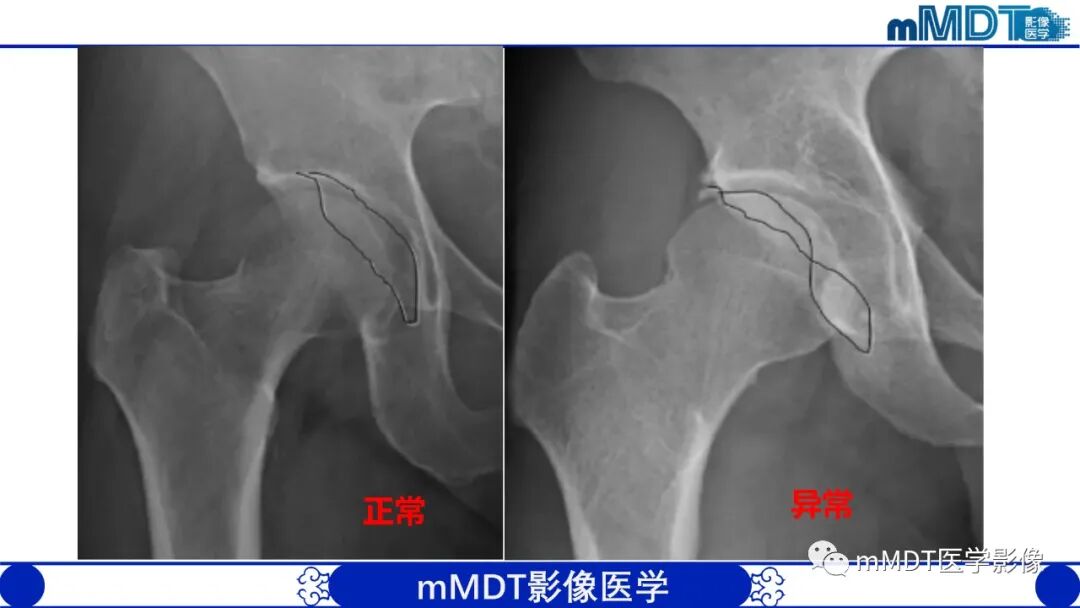

1.X线平片对本病的诊断是重要的,还应作相关测量,包括髋臼角、CE角、髋臼覆盖率(股骨头裸露程度)等。成人以测量CE角较为准确,而且简便。

2.在骨盆前后位片上髋臼顶短小,CE角小于30度,伴或不伴有髋臼倾斜度过大(髋臼角大于45度),股骨头裸露25%以上,可诊断为髋臼发育不良。需要注意的是,有时髋臼边缘继发骨性增生,使髋臼外缘代偿性加宽(假臼缘形成),可表现为CE角减小不明显甚至不变小;而股骨头肥大、变形、外移或半脱位时则可出现由于股骨头中心外移造成的CE角过度变小和股骨头裸露增大,在这种情况下,观察髋臼角的增大及髋臼深度的改变有重要意义。